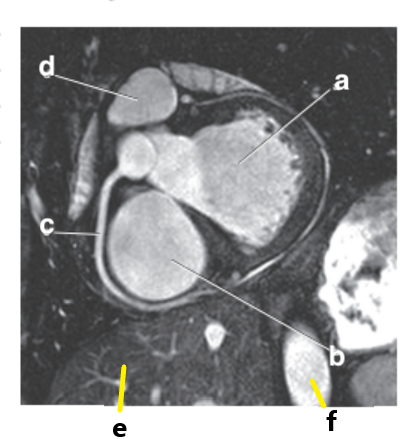

What is letter a ?

Left Ventricle

Left atrium

What is letter b ?

Right ventricle

What is letter c ?

What is letter d ?

Bicuspid valve / LT AV valve